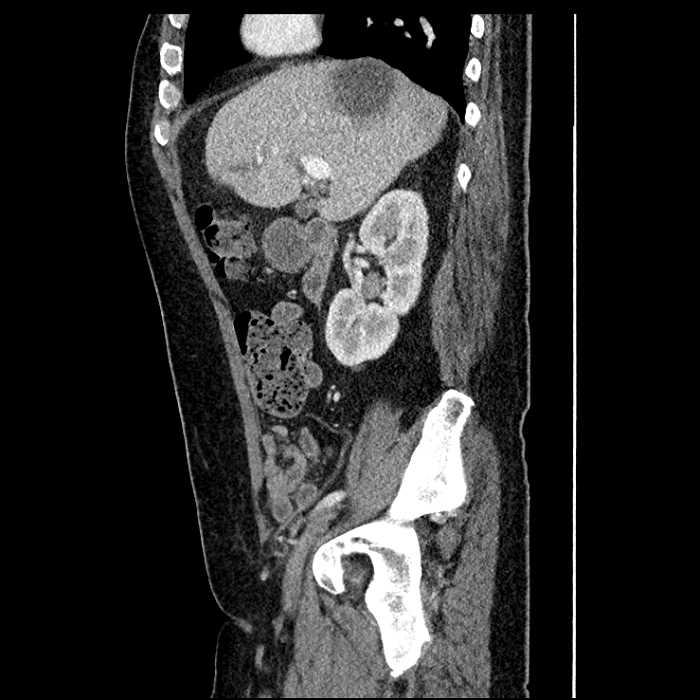

Acute sigmoid diverticulitis complicated by a small contained perforation and a large abscess in the right hepatic lobe. Additional small subcapsular abscesses along the anterior margin of the left hepatic lobe.

• The classic CT imaging appearance is a double target sign with internal low density surrounded by an internal enhancing rim (capsule) and a low density external rim (edema)

Hepatic abscess showing the double target sign with low density internally surrounded by a thin inner enhancing rim (red arrow) and ill-defined outer low density rim (yellow arrow). Blue arrow indicates an internal septation. Red arrows: additional smaller subcapsular abscesses. Red arrow: focal contained perforation associated with diverticulitis.